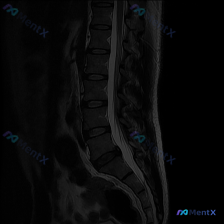

- 序列:腰椎MRI T2矢状位

- 明确发现:L1/2到L5/S1椎间盘弥漫性脱水低信号,L4/L5、L5/S1向后膨出压迫硬膜囊前缘,部分椎体终板有许莫氏结节,生理前凸存在,序列尚可,无明显骨折脱位或严重椎管狭窄

- 椎旁软组织无脓肿、血肿或肿块影